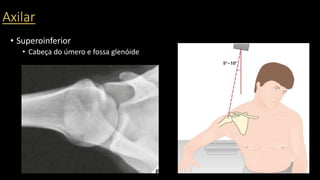

O documento aborda lesões no ombro, dividindo-as por faixas etárias: fraturas de clavícula em crianças, luxações em adultos e fraturas do úmero proximal em idosos. Descreve também técnicas de avaliação radiográfica e suas variações, incluindo incidências específicas para diagnóstico. Além disso, são mencionados métodos de imagem alternativos para a avaliação de partes moles e condições articulares.